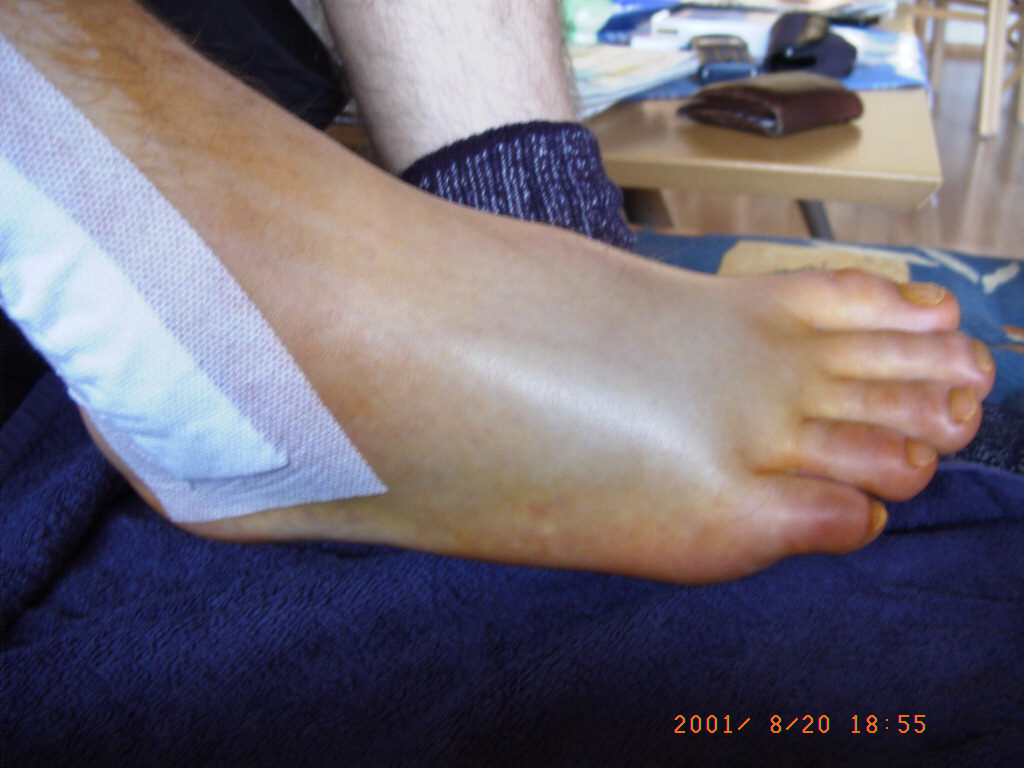

Am 12.08.2001 hab ich mir beim Fußballspiel den rechten Außenknöchel gebrochen !

Die Fäden wurden am 28.08.2001 gezogen.

Sechs Wochen durfte ich nicht auftreten (keine Belastung). Ab der siebten Woche (26.09.2001) durfte mit 20kg und ab der achten Woche (03.10.2001) mit 40kg belastet werden.